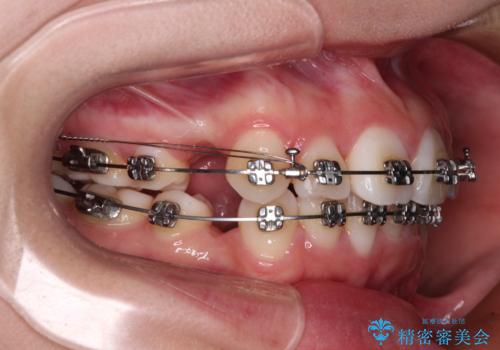

- メタルブラケット

- 歯のデコボコや八重歯、クロスバイトを気にして来院された患者様です。

上下左右第一小臼歯4本を抜歯し、ワイヤー装置にて歯列を整え、さらには少しでも口元を引っ込めるよう矯正治療を行うこととしました。